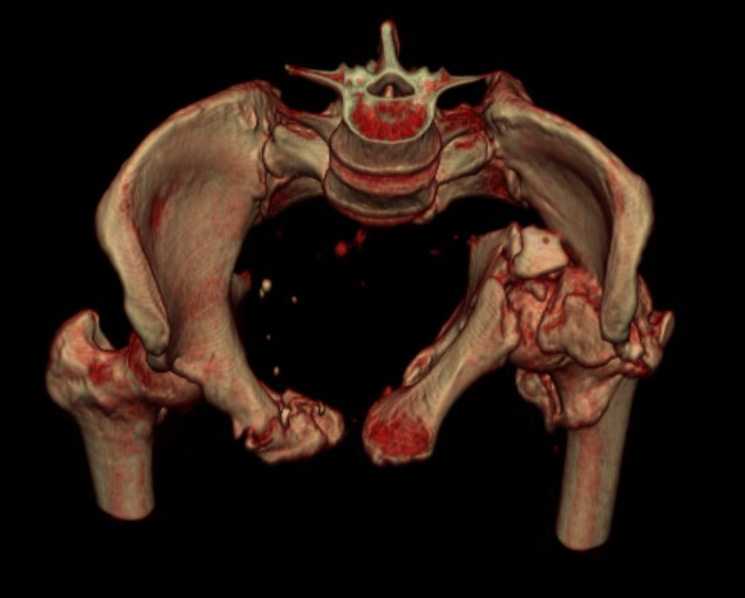

Больная 43 года (промышленный альпинист), 28.07.08 в результате падения с 5 этажа получила политравму: Перелом свода и основания черепа. Вертикально-нестабильное повреждение таза, осложнённое разрывом мочевого пузыря. Чрезвертельный перелом левого бедра. Перелом правой таранной кости, переломовывих правой кубовидной кости. Тупая травма живота, разрыв печени, ушиб почек. Забрюшинная гематома. В день травмы - лапаротомия, ушивание ран печени. Разрыв мочевого пузыря не диагностирован. Течение болезни осложнилось развитием мочевого затёка и обширной пред- и забрюшинной флегмоны, сформировался свищ мочевого пузыря. 19.8.2008 вскрытие, дренировние флегмоны, ревизия мочевого пузыря, обтурация мочевого свища (свищ закрылся в октябре), 1.10.2008 некрэктомия, пластика по Шеде-Лидскому правой кубовидной кости. По результатам КТ диагностирован рак правой почки (диагностическая находка), 8.10.2008 нефрэктомия справа. Переломы велись консервативно. Имеется вертикальное смещение левой половины таза с выраженным отведением крыла (клинически подвижности нет), несросшийся низкий двухколонный перелом левой вертлужной впадины с потерей конгруэнтности, укорочение около5 см, застарелый разрыв лонного сочленения, неправильно сросшиеся переломы обеих ветвей правой лонной кости с укорочением, патологическая подвижность лоно-седалищного фрагмента слева. Правая нижняя конечность неопорна, несмотря на то, что лежа прямую ногу поднимает, ходит на левой ноге (ортопедическая обувь) с костылями, справа тазобедренный ортез. Седалищные нервы работают.Урологи отпустили больную на 6 мес.

с большей вероятностью пациентка придет к эндопротезированию тазобедренного сустава, поэтому необходимо создать надежную "опору" сзади и подготовить бедро к имплантации любой классической ножки.ИМО бедренной кости GN, АНФ на таз,по необходимости остеотомия крестца, восстановление конфигурации задних отделов и устранение вертикального смещения половины таза. дождаться сращения крестца и бедренной кости. второй этап эндопротезирование: ножка цвай-мюллер или спаторно,ацетабулярно онкологическое антипротрузионное кольцо левое либо ацетабулярный компонент по индивидуальным параметрам для протезирования после резекции лонной седалищной костей и вертлужной впадины при онкопатологии. в кольцо пару трения металл\металл с цементной чашкой IMPLANTCAST, т.к. пациентка молодая.лонные кости можно оставить в покое, какой никакой рубец есть. с уважением Сергей.